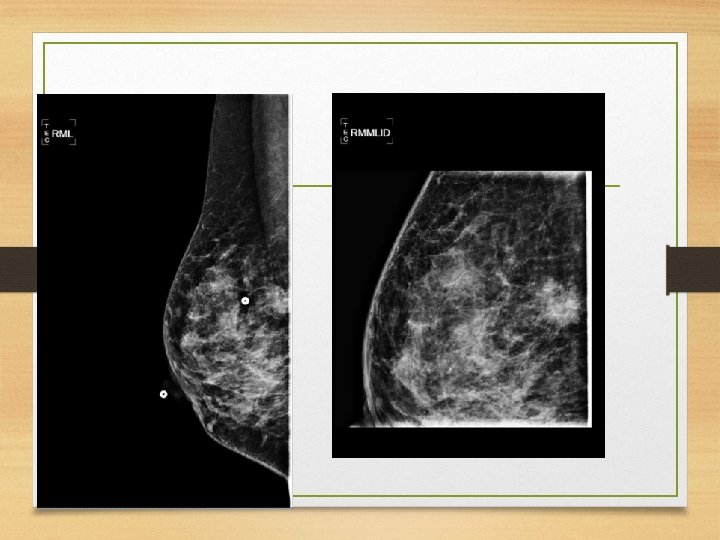

Oblicuo medio lateral • Paciente de pie o sentada. • Ambas mamas por separado. • El rayo central entra perpendicular al músculo pectoral de la paciente. • Se debe determinar el grado de oblicuidad del musculo pectoral entre 45 y 60 grados.

• La paciente de frente al mastógrafo, coloca el brazo del lado evaluado hacia adelante y la mano hacia el frente. • Se tracciona la mama y el m. pectoral anterior y medialmente, lejos de la pared torácica. • Aplicar compresión con la mama lejos de la pared torácica y hacia arriba. • El borde superior debajo de la clavícula y el borde inferior incluirá el pliegue infra mamario • La paciente puede retraer la mama opuesta con la otra mano.

• Criterios de evaluación: • a) Debe verse todo el • • • tejido mamario b) el musculo pectoral se debe encontrar a la altura del pezón c) el patrón del parénquima debe observarse a 90 grados d)Demostrar pliegue inframamario e) región axilar visible f) pezón perfilado g) área glandular y adiposa adecuadamente penetradas.